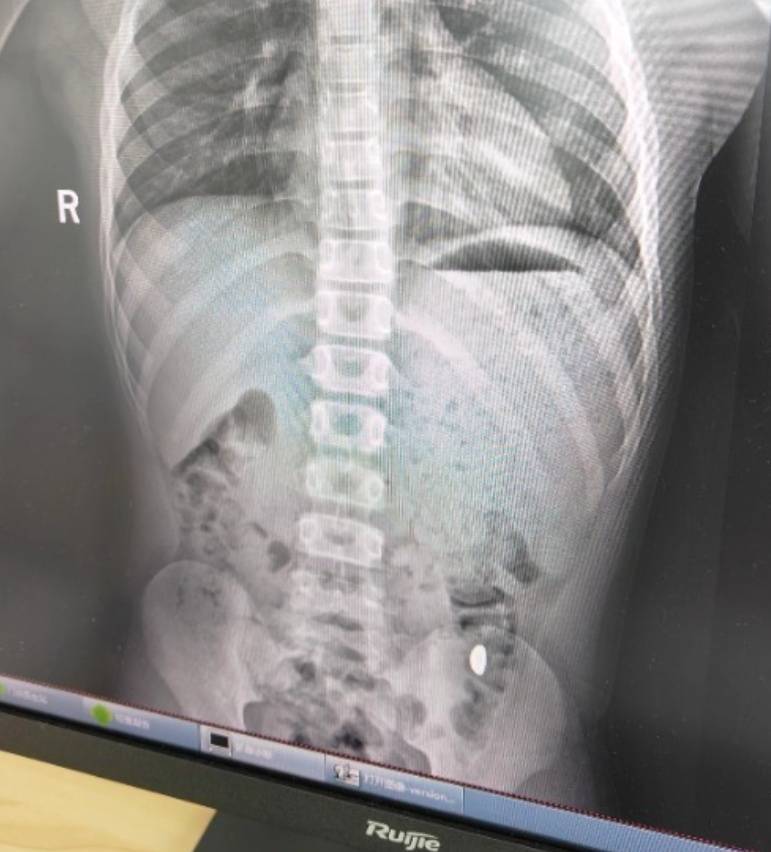

右下加亮点为金豆欧易平台。